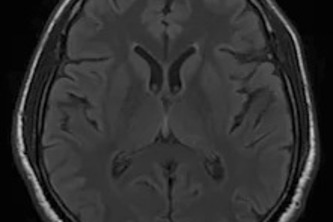

AI-powered deep learning model for accurate and automated brain tumor detection from MRI scans, enabling faster diagnosis and supporting medical professionals in early treatment decisions.

Automated MRI tumor detection platform using AI and image processing to deliver fast, reliable, and accessible healthcare.

Smart MRI Analysis for Early Tumor Diagnosis